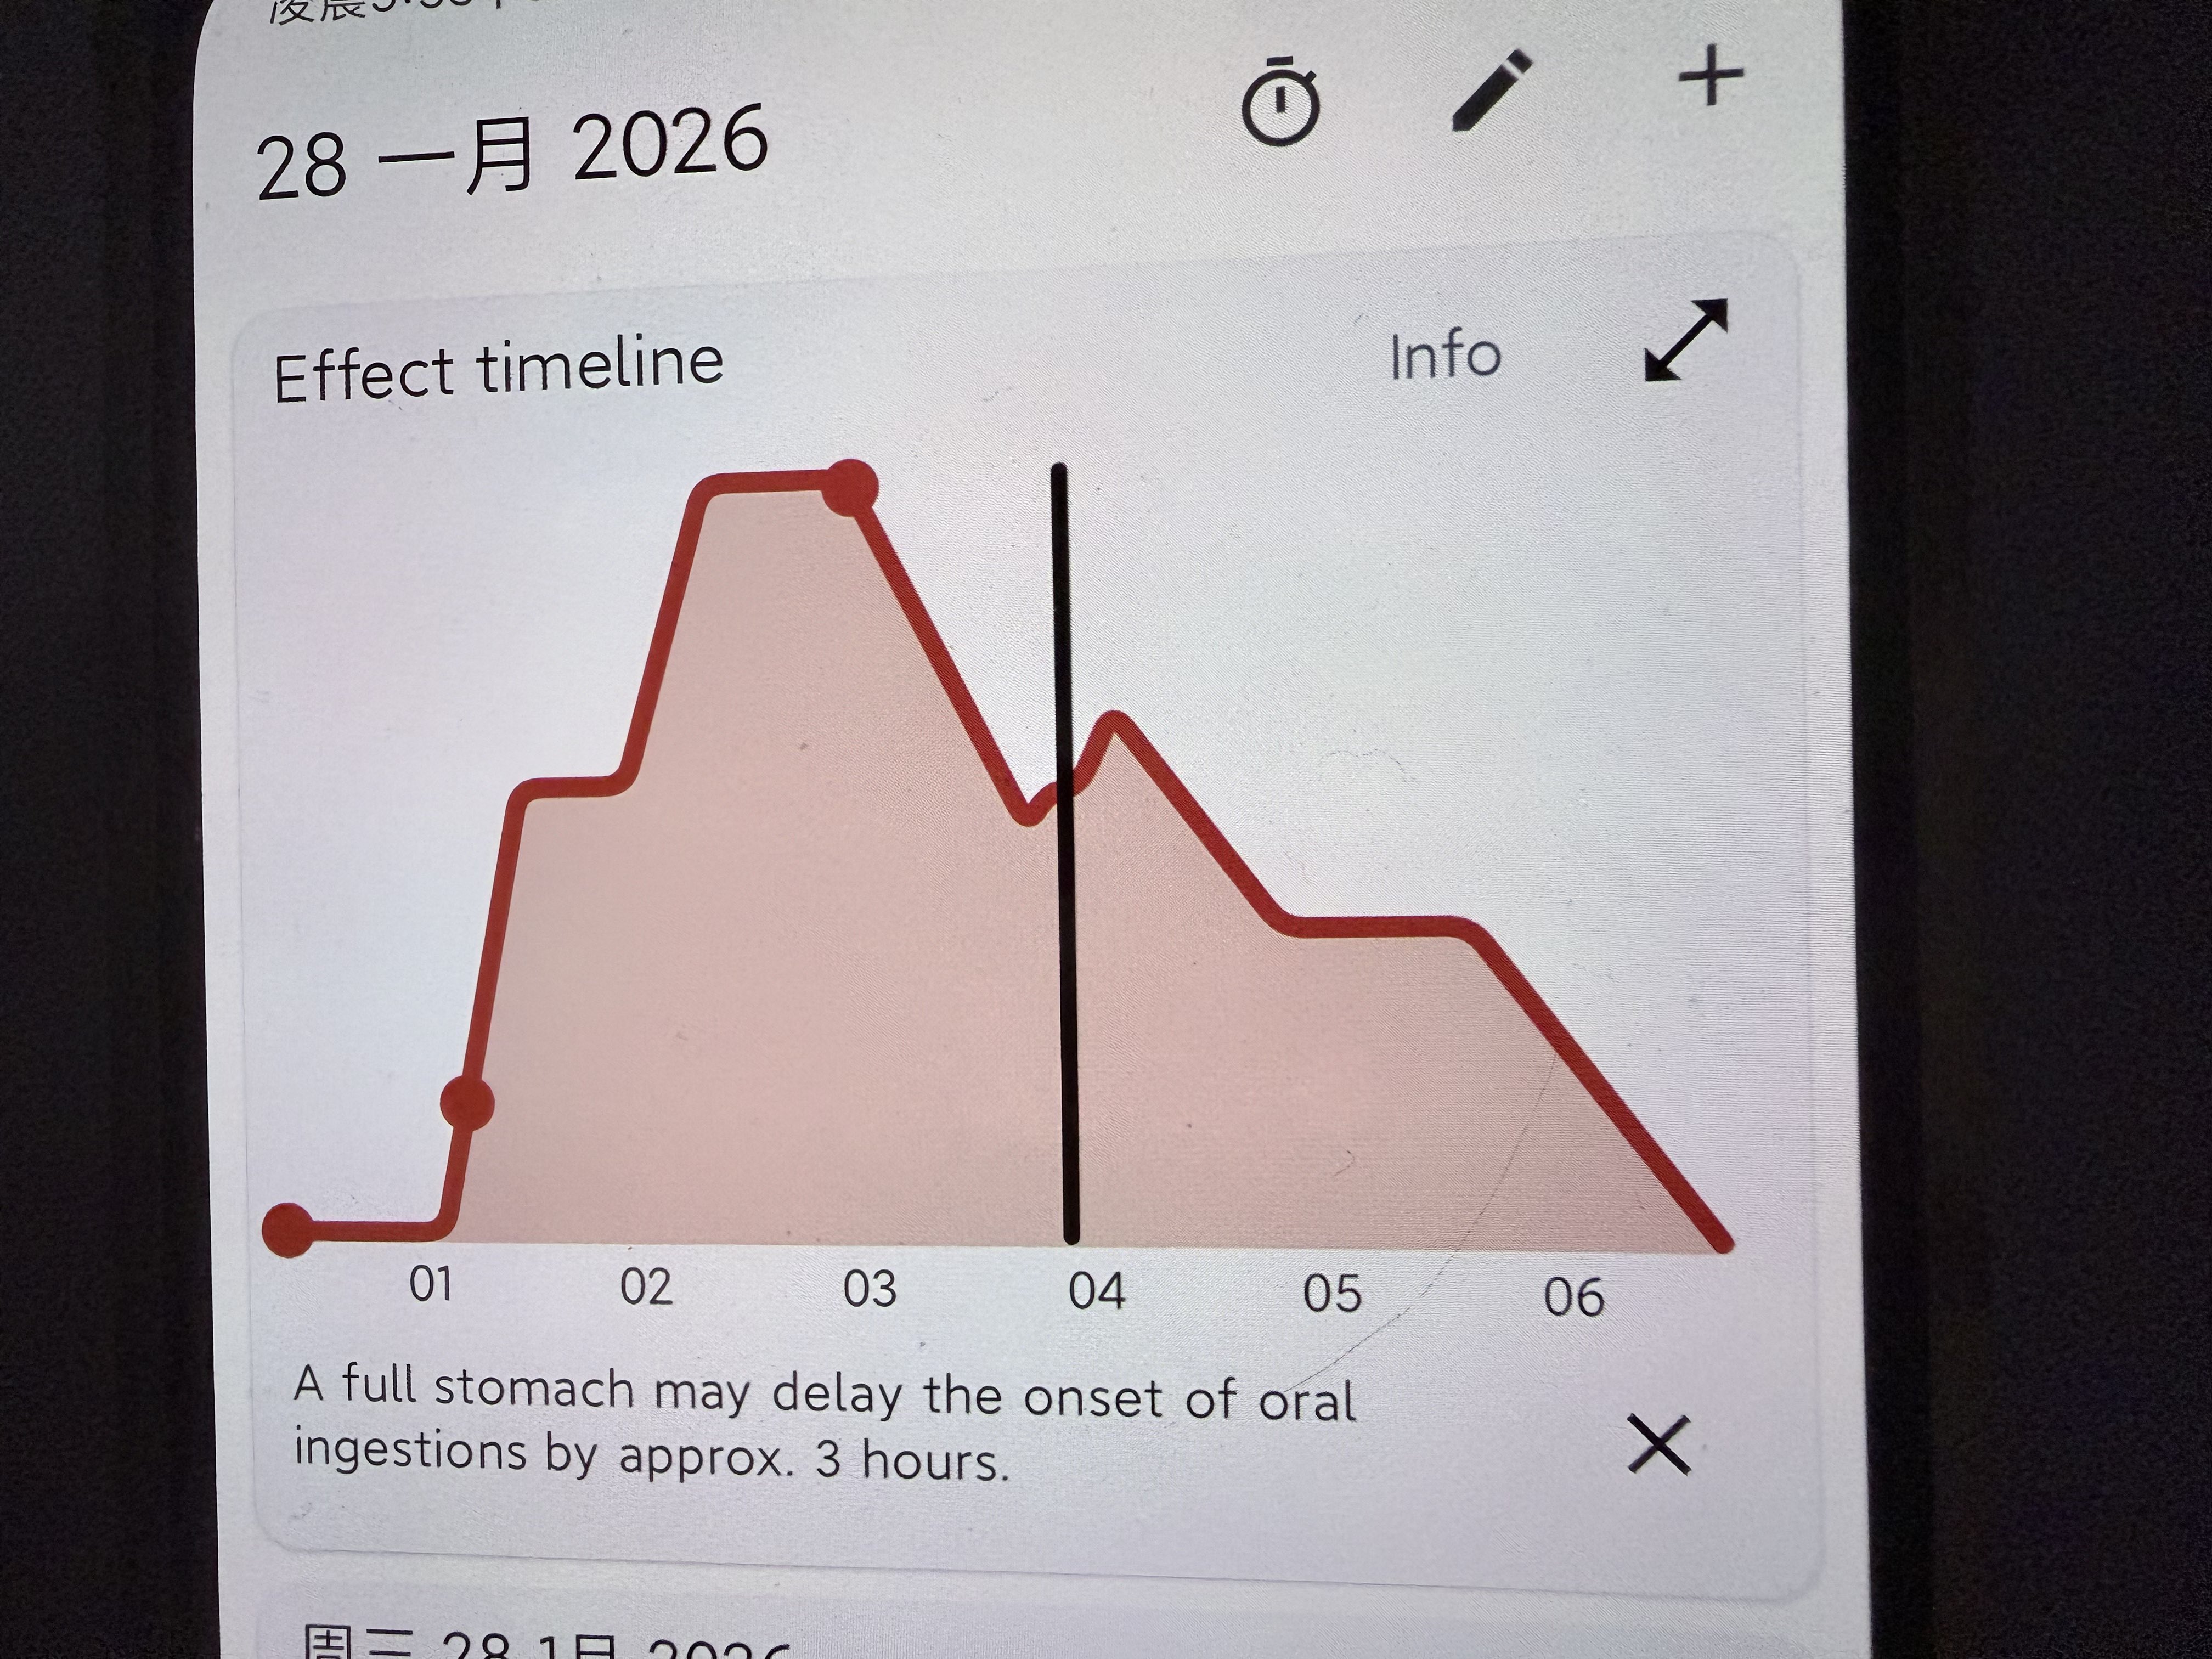

2026-01-22 19:09:20 UTC

化学带来的幸福感不需要外在环境的配合,它直接作用于你感知幸福的能力本身…